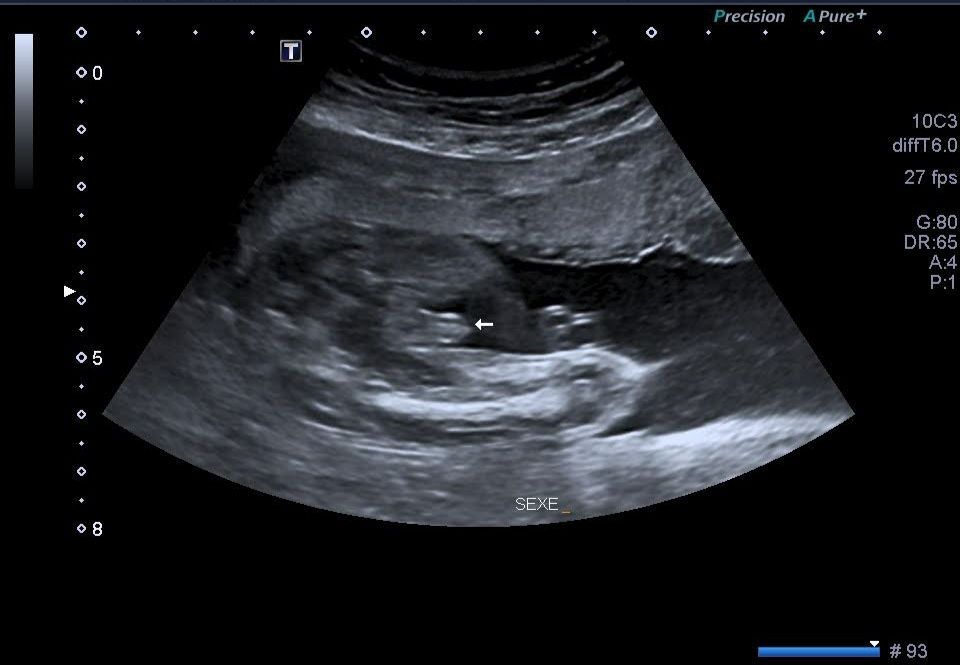

Кого вы видите на этом УЗИ? Мальчика или девочку?)

На втором фото вроде как мальчик, но где яички и если приблизить то видно как полоску половых губ))

это мальчик, у меня на узи по определению пола такая же картинка была:)

Мальчик. Отлично видно мошонку. Яички опускаются почти перед родами, или даже после родов

У девочки ничего не торчит между ножек ,похоже на мальчика (если не пуповина)